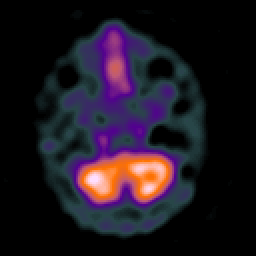

Huntington's Chorea, MR -- Slice #2